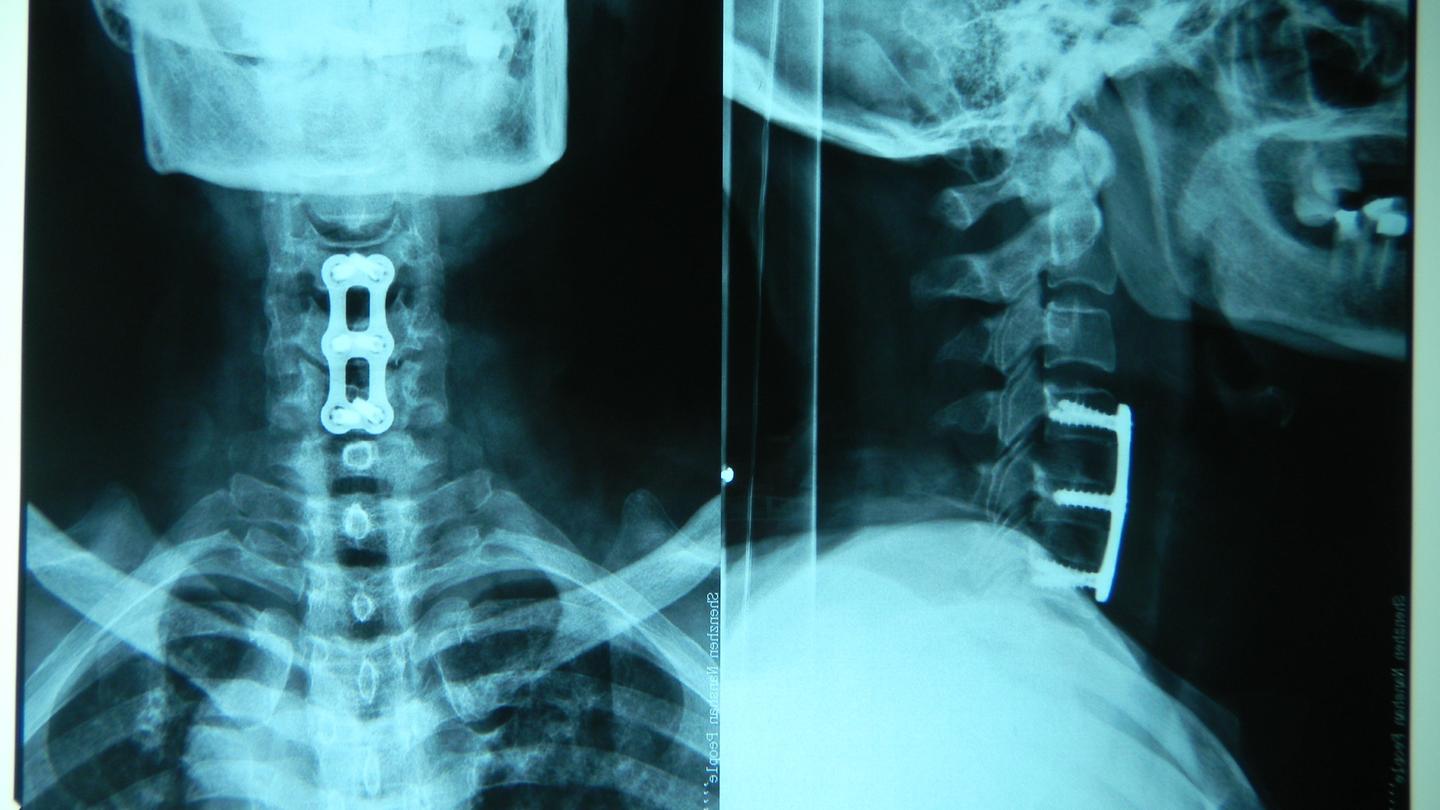

图片尺寸3968x2232

关于食管压迫型颈椎病的简单介绍

图片尺寸640x480